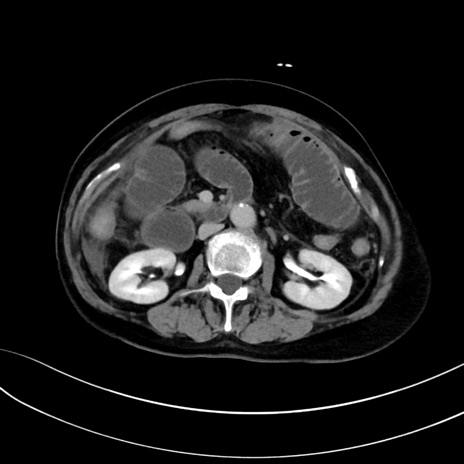

症例13 CT(横断像)1日半後

(冠状断像)1日半後